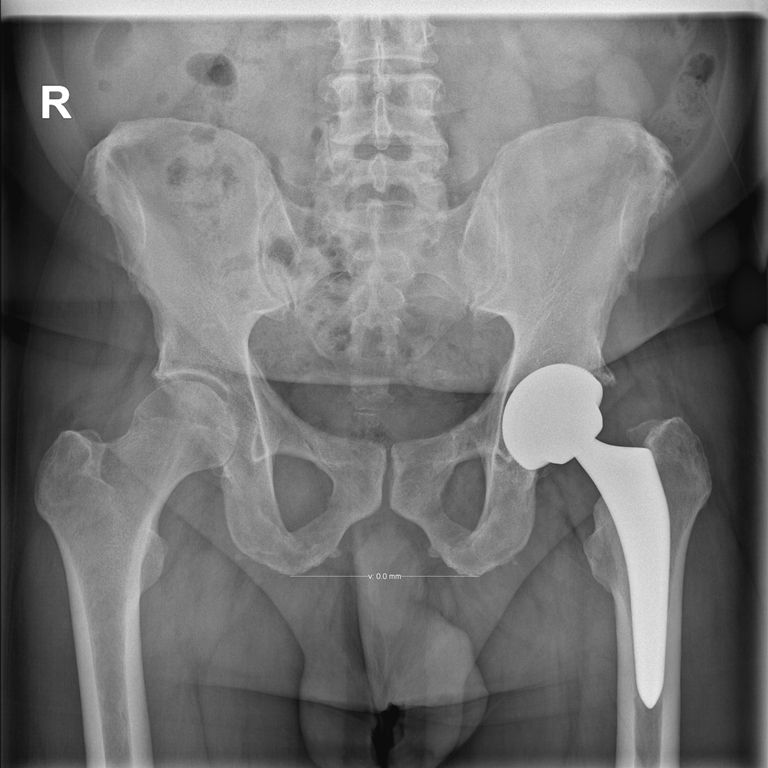

Meine Frage, ob ich meine Prothese sehen könnte, wurde aus Sterilitätsgründen verneint, aber ich habe mich recht gut vorbereitet, daher kann ich hier auch ein Referenzbild zeigen. Die eigene wäre aber trotzdem interessant gewesen.

Bei fachgerechter Operation (siehe dazu das Kapitel am Ende) beträgt die Lebensdauer der Hüft-TEP (Totalendoprothese des Hüftgelenks) heute 20 bis 25 Jahre, oft sogar länger. Offiziell werden trotzdem 15 Jahre kommuniziert, ich habe aber mit einigen Leuten gesprochen, die ihre Endoprothese ohne Probleme schon länger als 20 Jahre haben.

Gleich um 7 Uhr, noch vor dem Frühstück, wurde ich zum Röntgen gefahren. Leider habe ich mein Handy nicht mitgenommen, so kann ich euch kein Bild meines neuen Gelenks zeigen. Kurz nach dem Frühstück kam dann auch noch geistlicher Beistand mit einem sehr guten kurzen Gespräch. Bei der Visite wurde mir bestätigt, daß ich am nächsten Tag, dem Freitag, heim gehen kann und die Medikation für die nächsten Wochen erklärt. Mit der Ergotherapeutin konnte ich auch noch das Ein- und Aussteigen aus der Badewanne üben, ist leichter als ich dachte, ob es zu Hause auch so gut klappt? Die Narbe ist zwar nicht sehr groß, dafür war der Bluterguss rundherum umso größer. Regelmäßige Kühlung mit einem Coolpack sollte ihn möglichst bald verkleinern. Die Schmerzen waren minimal, das ist natürlich auch den 4 Schmerztabletten pro Tag zu verdanken. So sprach nichts mehr gegen das Heimgehen morgen, nachdem ich von einer Apothekenangestellten auch noch mit meinen Medikamenten für die nächsten 2 Wochen versorgt worden war.